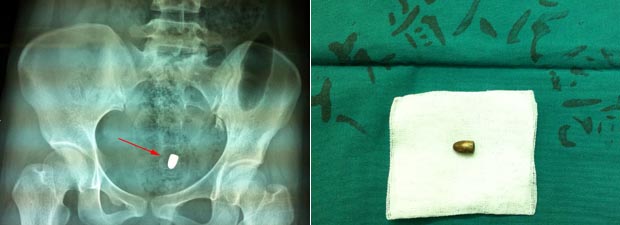

X光片显示,子弹位于盆腔内并左侧髂骨粉碎性骨折。胃肠外科当天值班医生王俊江前去会诊。王医生分析患者病情:子弹大概位于盆腔子宫前、膀胱后方。他随即向二线姚学清主任及科主任林锋主任汇报病情,明确是否合并腹腔脏器损伤可能,要求妇科、泌尿科、骨科等相关科室予以会诊。

经过ICU的积极准备,在麻醉科和手术室的全力配合下,30日中午,由王俊江、吴德庆医师共同主刀,实施腹腔镜探查。根据术前CT影像,于左侧子宫前方、膀胱左后壁后方找到约10x6mm圆锥形子弹头一枚。同时发现弹道渗血,主刀医生给予了电凝和止血纱布填塞止血,仔细观察无明显出血后留置腹腔引流1根,术中最大切口1cm。